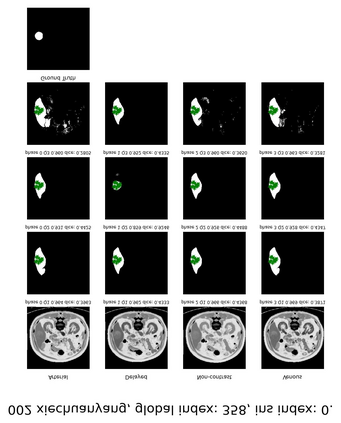

Learning to segmentation without large-scale samples is an inherent capability of human. Recently, Segment Anything Model (SAM) performs the significant zero-shot image segmentation, attracting considerable attention from the computer vision community. Here, we investigate the capability of SAM for medical image analysis, especially for multi-phase liver tumor segmentation (MPLiTS), in terms of prompts, data resolution, phases. Experimental results demonstrate that there might be a large gap between SAM and expected performance. Fortunately, the qualitative results show that SAM is a powerful annotation tool for the community of interactive medical image segmentation.